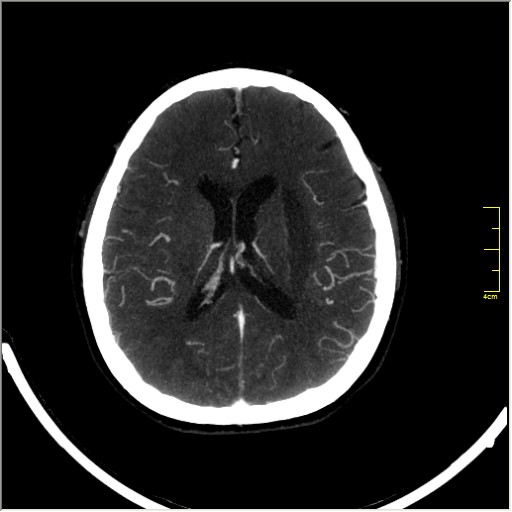

КТ ангиография головного мозга

Стандартная процедура в современной работе КТ кабинета, весьма несложна в исполнении.

Сканы представленны в режиме MIP.